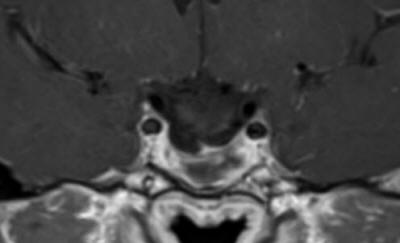

In prone position with the use of IOM ISIS, laminectomy of C2-3 and partial of C1 was achieved. The dura was opened slightly right parallel to the midline. The dumbbell-shaped appearance of the tumor was due to right C2 anterior and posterior rootlets, which were constricting the tumor and they were preserved to the end of surgery. The matrix of the meningioma was the right lateral wall of the dura, which was coagulated and piece-meal resection of the tumor was performed. MEP was troubleshooting and not informative. After the resection of the tumor a tiny piece and the emergence of the right C1 was removed trying during that to preserve the rootlets. Using MultiGen, bipolar motor stimulation of right C2 was achieved with 1.0 V. Motor stimulation of the right side of the spinal cord and a brisk response of the right upper and lower limbs was achieved above the tumor resection area. Irrigation of the area with 1 ampoule Papaverine diluted with 20 ml saline. The dura was closed water-tightly. Routine closure of the wound. The patient was sent to MRI before extubation.

Fig-17: Anatomical architecture of the spinal cord at C2-C3 level.

Fig-20: Check MRI before extubation.

Fig-21: Check MRI before extubation,